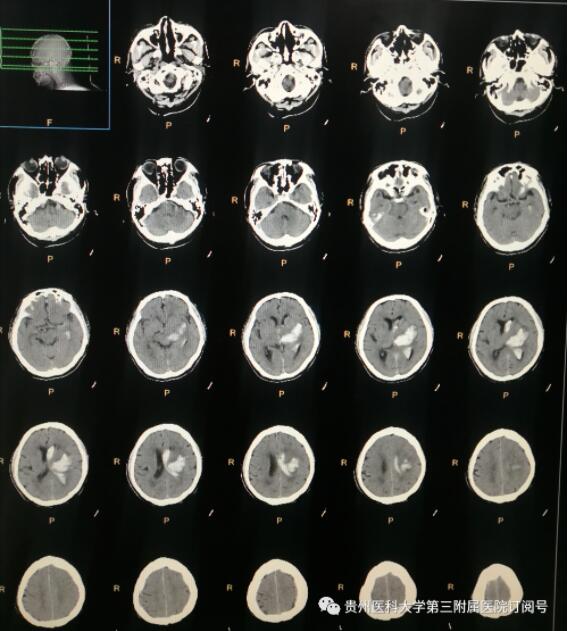

12月13日,随着“120”急促的警报声由远及近,一位年过七旬、突发意识障碍的老人被紧急送入我院神经外科。患者入院时已发病7个多小时,神志呈浅昏迷状,右侧肢体在刺痛状态下仍不能动,左侧肢体在刺痛下可回缩。入院头颅CT提示“左侧背侧丘脑——基底节区脑出血并破入脑室,血肿量约30ml,周围水肿带形成,轻度脑疝形成”,双侧瞳孔正圆等大,直径约1.5mm,对光反射迟钝,右侧巴宾斯基征阳性。因患者系基底节区脑出血并破入脑室,病情危重,需降低其颅内压,调整血压,给予对症支持治疗。并急需行手术,用以清除血肿减压,避免脑疝进一步损伤脑组织。神经外科副主任、副主任医师王勇团队为患者行内镜下左侧基底节区血肿外引流术+硬脑膜修补术+颅骨修补术+右侧侧脑室穿刺血肿外引流术+气管切开术。手术顺利。据了解,该手术属于四级手术,我院神经外科已常规开展。

术前头颅CT